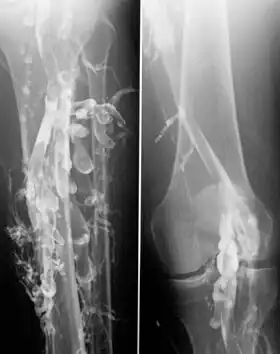

Venography in a patient with deep vein thrombosis

Contrast venography is the gold standard for judging diagnostic imaging methods for deep vein thrombosis; although, because of its cost, invasiveness, and other limitations this test is rarely performed.[1]